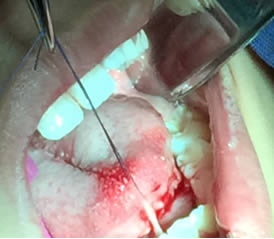

• Se pasa una sutura sin anudar en la punta de la lengua para traccionar la misma y facilitar las maniobras quirúrgicas. Posteriormente se utilizan dos pinzas de mosco, una curva y una recta pinzando el frenillo en su borde superior e inferior para limitar sus bordes. Figuras 3 y 4.

Figura 3. Sutura sin anudar en punta de la lengua

Figura 4. Pinzado del frenillo